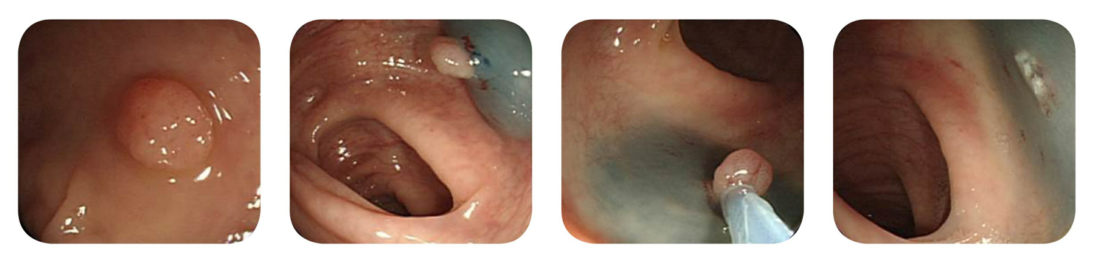

모든 대장암은 용종에서부터 시작이 되며, 내시경 검사시 용종이 발견된다면, 병원에서는 그 용종을 검사기관에 맡기며, 약 7일 후 그 결과를 통보받게 됩니다.

용종이 점점 커지고, 악화되면 암으로 진화가 되며, 암이 진화되면서 최악의 경우에는 생명을 빼앗길 가능성도 존재하게 됩니다. 용종이 2cm 가 넘어가게 된다면 대장암으로 전이되는 가능성이 높으며, 우리가 먹는 음식물 속에 존재하는 발암물질과 같은 환경적인 요인과 유전적인 취약성, 스트레스가 복합적으로 작용하여 대장점막의 세포에 변성이 일어나 비정상적인 성장을 하게 되면서 용종이 발생하게 됩니다.